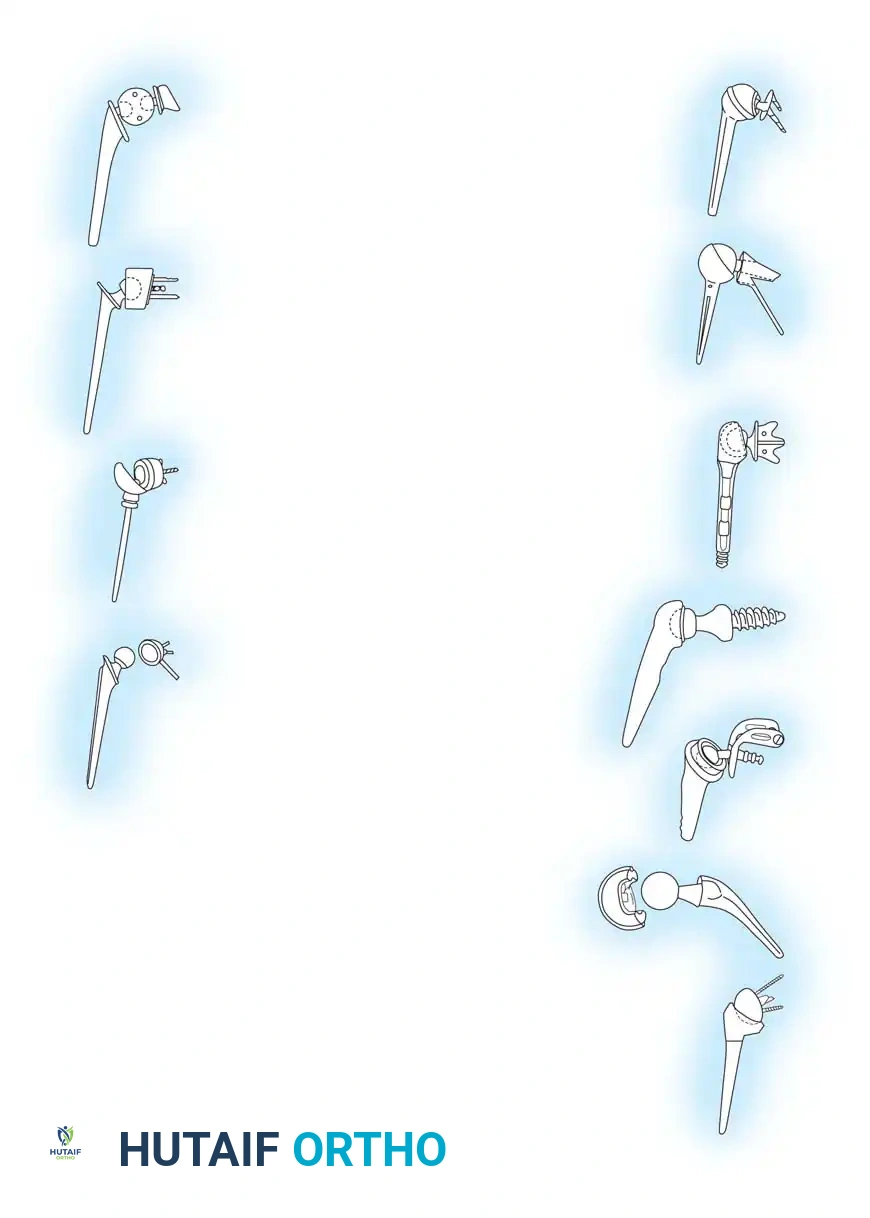

The genesis of shoulder arthroplasty dates back to 1893 when French surgeon J.E. Péan implanted a platinum and rubber prosthesis for a glenohumeral joint destroyed by tuberculosis. Modern shoulder arthroplasty, however, was pioneered in the early 1950s by Charles S. Neer II, who introduced an unconstrained cobalt-chromium alloy (Vitallium) humeral head prosthesis for complex proximal humerus fractures.

By 1974, Neer developed the Neer II humeral prosthesis, modifying it to conform to a high-density polyethylene glenoid component, thereby birthing the modern Total Shoulder Arthroplasty (TSA).

Clinical Pearl: The development and subsequent failure of early constrained TSA systems stemmed from two false assumptions: (1) that most arthritic patients had deficient rotator cuffs, and (2) that rotator cuff function could be effectively replaced by a fixed fulcrum. This led to catastrophic glenoid loosening, paving the way for unconstrained anatomical designs and, eventually, the reverse ball-and-socket concept.

In the 1990s, emphasis shifted toward restoring normal kinematics through modular humeral components, allowing surgeons to replicate individual patient anatomy. Today, the Reverse Total Shoulder Arthroplasty (rTSA), based on the biomechanical principles of Paul Grammont, dominates the landscape for patients with rotator cuff deficiency.

Types of Elbow Arthroplasty

- Linked (Semiconstrained): The humeral and ulnar components are physically connected via a locking pin. This is the workhorse for most Total Elbow Arthroplasties (TEA), especially in cases of ligamentous insufficiency or severe bone loss.

- Unlinked: Relies entirely on the patient's native collateral ligaments and soft tissue envelope for stability. Rarely used today due to high rates of instability.

3. Canal Preparation and Implantation

The humeral and ulnar canals are sequentially broached.

- A cement restrictor is placed in both canals.

- Antibiotic-loaded polymethylmethacrylate (PMMA) bone cement is injected in a retrograde fashion.

- The components are inserted, and the articulation is linked using the manufacturer-specific locking pin mechanism.